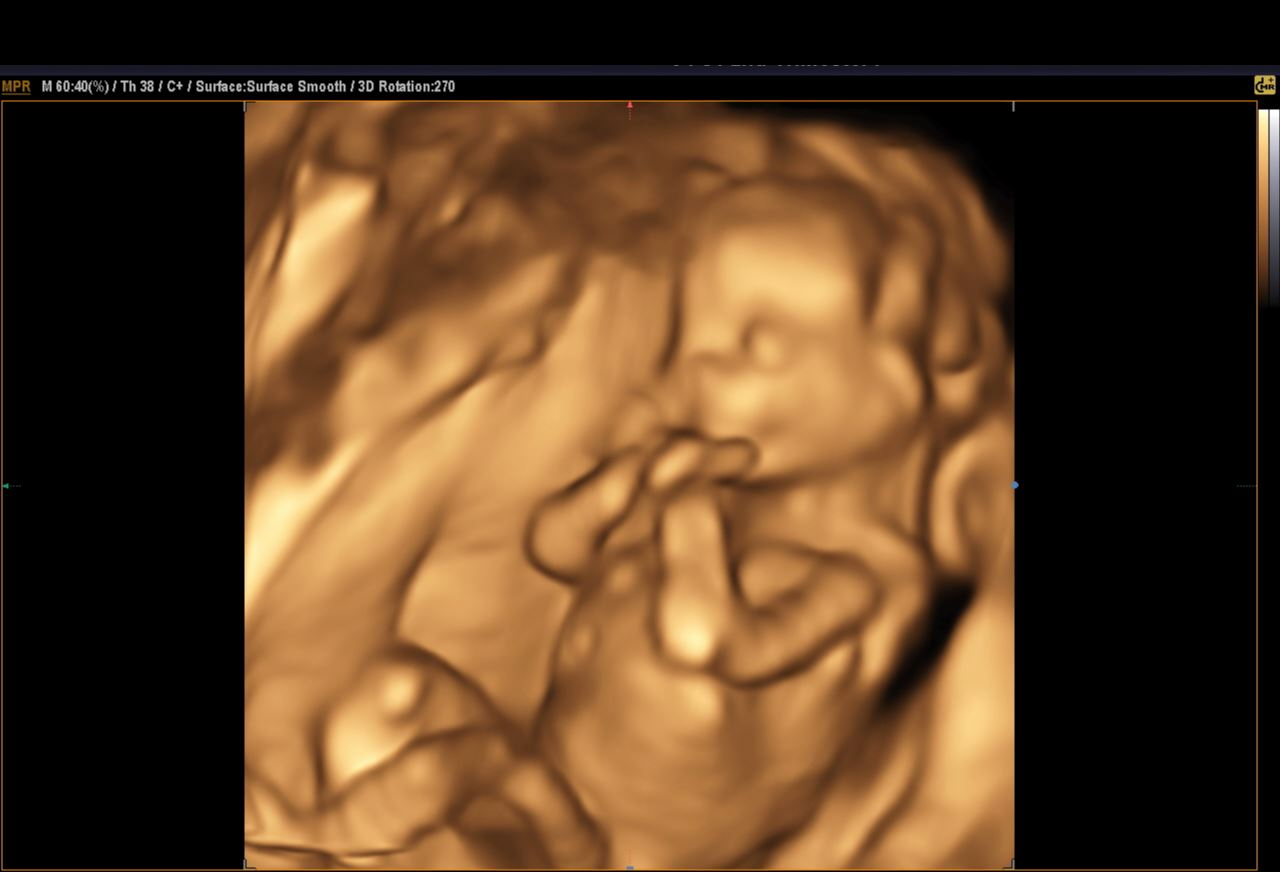

Wow @law_and_little1, is that 4D? He looks so cuuuute in there! Look at his little knee!